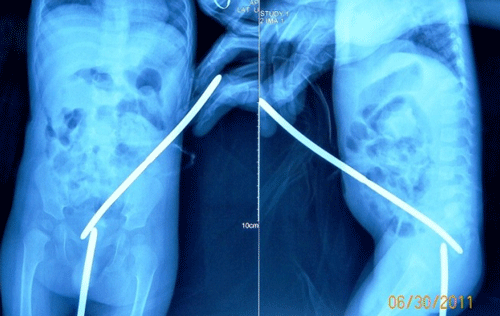

A 4-day-old, 1.7kg weight male neonate, born at term to a primigravida mother by normal vaginal delivery conducted by an untrained birth attendant, was brought with complaints of abdominal distension from D2 of life. There was no antenatal checkup or tetanus immunization, although the pregnancy and delivery was reported as normal. Although he had passed meconium on D1 of life, he had not passed any meconium for the previous three days. On examination, he was sick looking and had tachycardia (PR=160/min.) and tachypneic (RR=60/min.). Abdomen was grossly distended and tense. Hematological and biochemical investigations were normal. Abdominal X-ray showed massive pneumoperitoneum (Fig. 1). A clinical diagnosis of necrotizing enterocolitis Bell’s stage III was made. Keeping in view of the respiratory distress resulting from massive pneumoperitoneum, bilateral peritoneal drains were immediately put to deflate the abdomen.

The child was lost to follow up for a year. Per rectal examination revealed that rectum was totally obstructed about 4cm from anal verge. Distal cologram showed complete obstruction of rectum. The rectal obstruction was only few millimeters thick and simulated like congenital rectal atresia (Fig. 1).

Figure 1: Plain roentgenograms with bougies inserted from sigmoid colostomy and anal opening, revealing a thin membranous rectal atresia. |